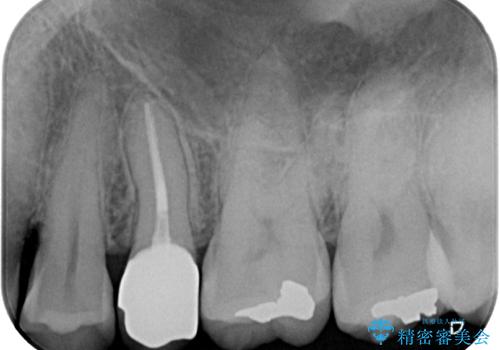

インプラント処置は、抜歯即時埋入を行い、十分な安定性が確認できたため、当日仮歯を装着しました。

インプラントが生着するのを待っている間に反対側の根管治療を行い、左右同時に補綴治療を行いました。

補綴治療後3ヶ月での経過は良好で、引き続き経過観察を行っていきます。